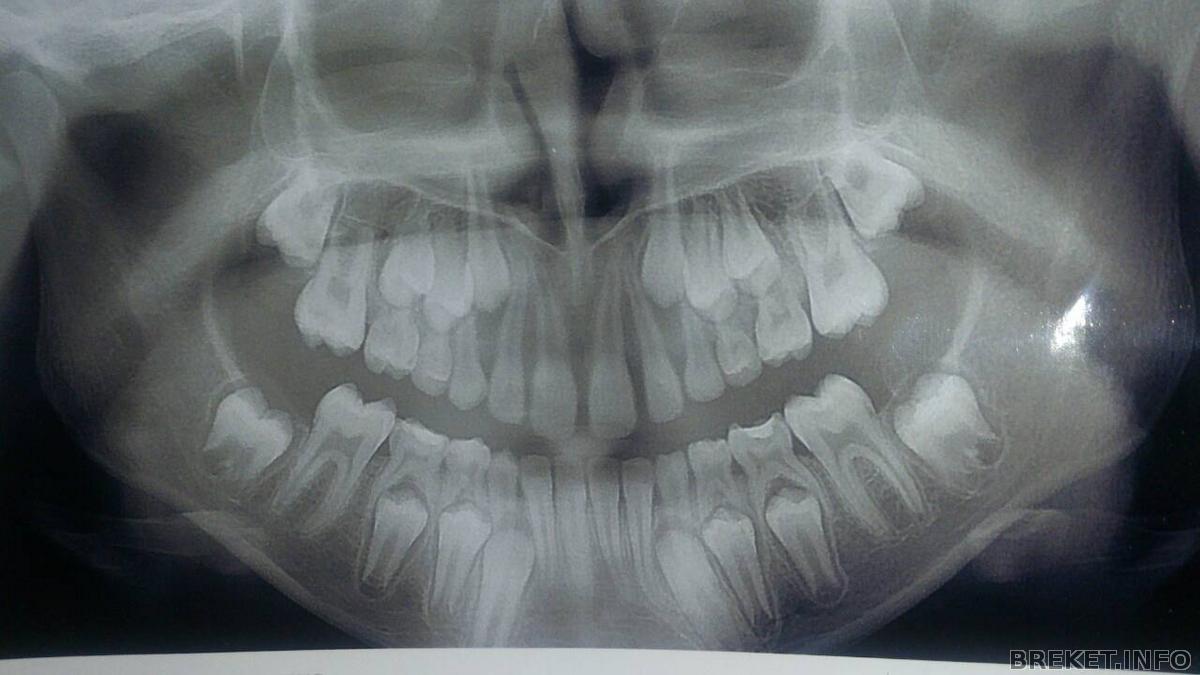

Панорамный снимок сделан 3 дня назад, дочке 10лет и 3мес, а зубы как у 7летней, со слов доктора Причина такого прикуса доктор сказал поздняя смена зубов (первые зубы вылезли в 9,5мес) К сожалению у меня есть только панорамный снимок, пока других врач не просил делать, поэтому максимально попыталась отобразить ситуацию на дополнительных фото.

К слову диагноз глубокий прикус, а точнее его причина (которую и надо найти и устранить) выявляется не по панорамному снимку, а по трг в боковой проекции